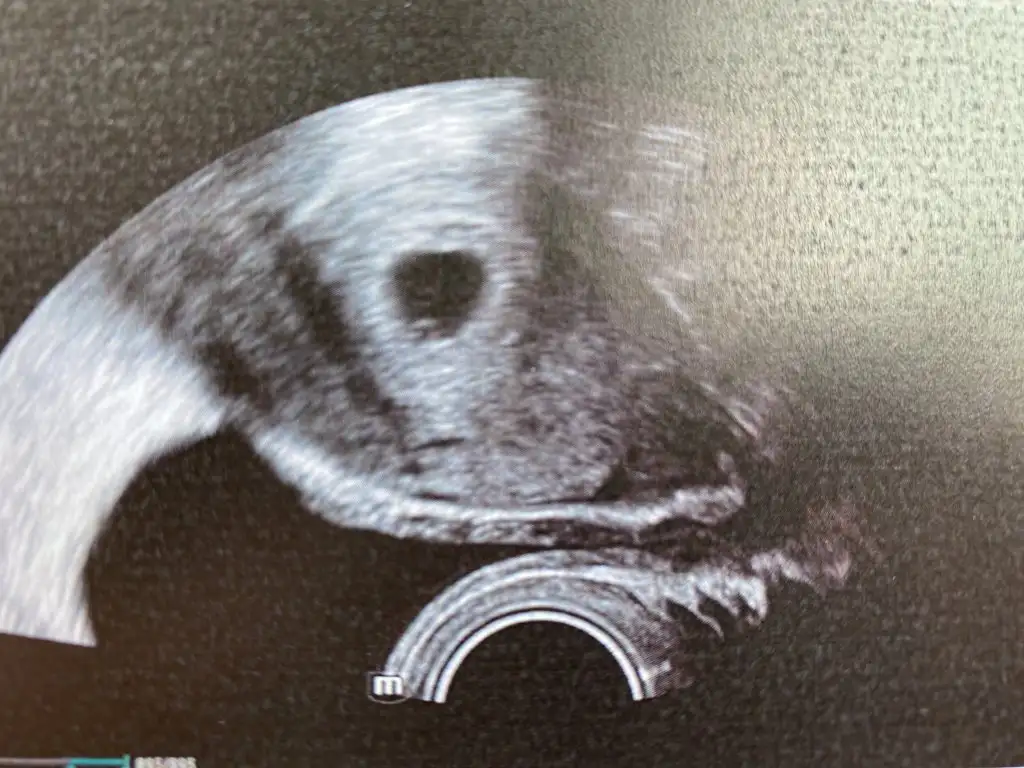

bak bunu netten aldım o soldaki yuvarlak yolk sac sende de aynısı var sadece sendeki cihazın çözünürlüğü düşük o yüzden bu kadar net değil

Eklentiler

• 8E5BCAE9-D2A9-4869-8155-0FF398305881.webp

8E5BCAE9-D2A9-4869-8155-0FF398305881.webp

16,6 KB · Görüntüleme: 293